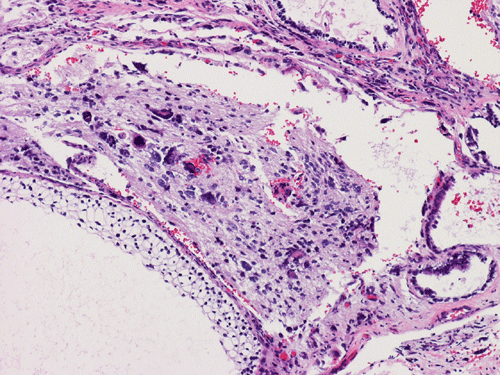

The entire specimen was submitted for histologic examination. The bulk (over 99%) of the tumor was composed predominantly of mature intestinal elements (Panel A, B, and C) and skin, respiratory type mucosa, cartilage, and small amount of mature neural parenchymal tissue of the central nervous system (Panel D and E). Neither immature nor malignant elements are present. Small microscopic foci of well demarcated, neural parenchymal tissue with increased atypia (arrow in panel F) are noted. On higher magnification (Panel G and H), these areas contain large, bizarre appearing cells with dark chromatin but no prominent nucleoli. There are also scant multinucleated cells and mineralized substances (arrow in Panel H). Another example of these foci is illustrated in Panel I, J, and K. These atypical foci comprised less than 1% of the volume of the tumor. They are all microscopic in size and show no evidence of expansion or invasion into the surrounding tissue.

The foci of neural parenchymal tissue with atypia raised the concern for malignancy. The atypical foci are all microscopic in size and well demarcated. They do not invade into the adjacent tissue. Although large atypical nuclei are noted, there is no prominent nucleoli. These changes are more consistent with ancient changes (degenerative atypia) or resulted from the chemotherapy prior to the resection. Identification of mineralized tissue is an additional features to confirm the benign biological potential of these foci. These foci are atypical but not embryonal and must be distinguished from immature element. With this token, the tumor is a mature teratoma but not an immature teratoma. Please see the discussion below for growing teratoma syndrome. This case is also unusual for an elevated alpha fetal-protein in serum with a lack of yolk sac tumor component in the tumor. Please see the discussion below for discussion.